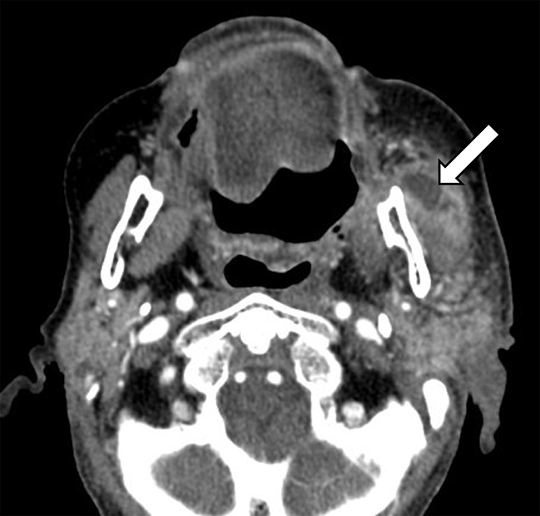

Corte axial de RM en imágenes ponderadas en T1 post- contraste. Paciente que consultó por caída de la comisura labial izquierda e hipoacusia derecha. Se identificó refuerzo post-contraste de los segmentos del nervio facial canalicular, laberíntico, ganglio geniculado y timpánico izquierdos, patognomónicos de la parálisis facial idiopática (o parálisis de Bell). En el conducto auditivo interno derecho, se observó una lesión focal redondeada hiperintensa compatible con schwannoma del nervio vestibular, principal diagnóstico diferencial de la parálisis de Bell.